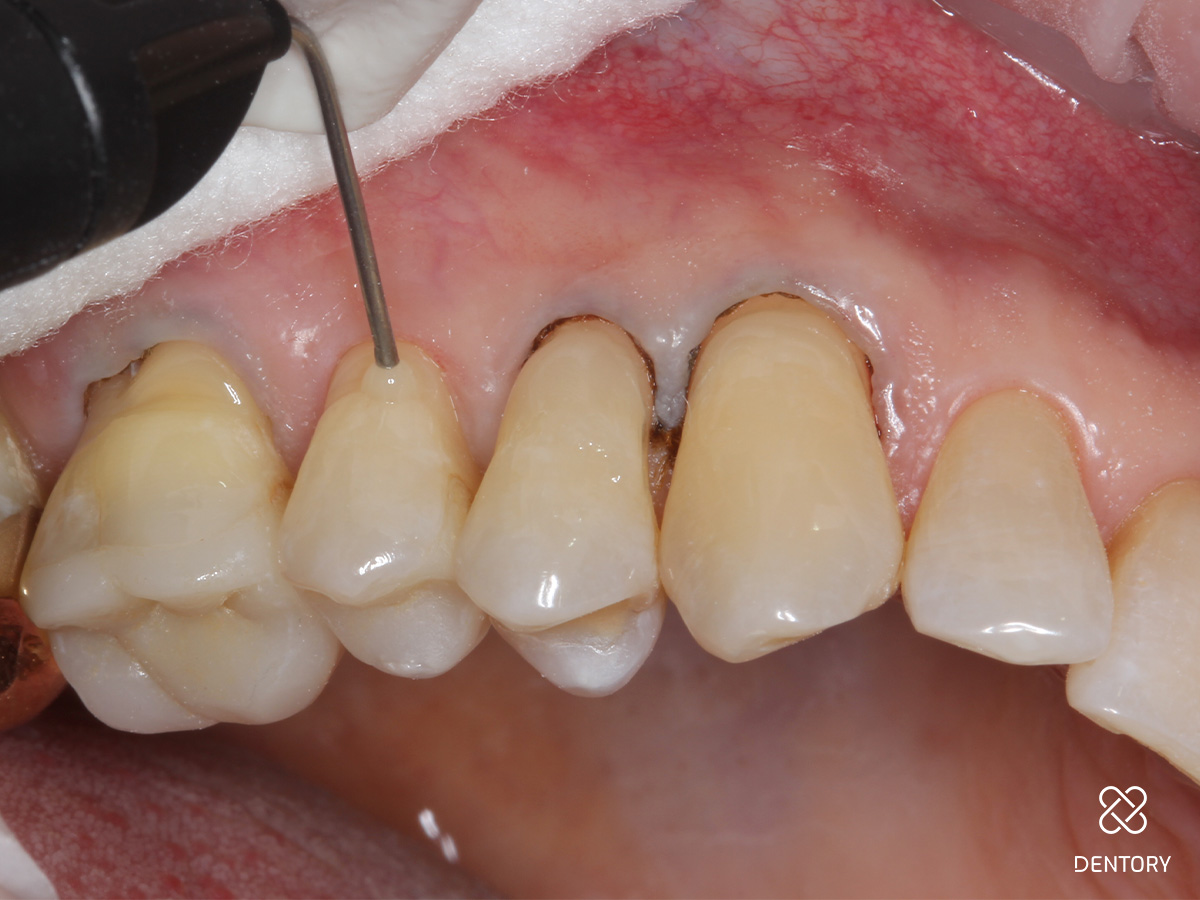

Abbildung 2

Beurteilung der Lage der Kavität nach zervikal. Liegt der Defekt supragingival, kann auf den Sulkus-Faden verzichtet werden. Liegt der Defekt äquigingival oder subgingival wird ein 00-Faden gelegt.